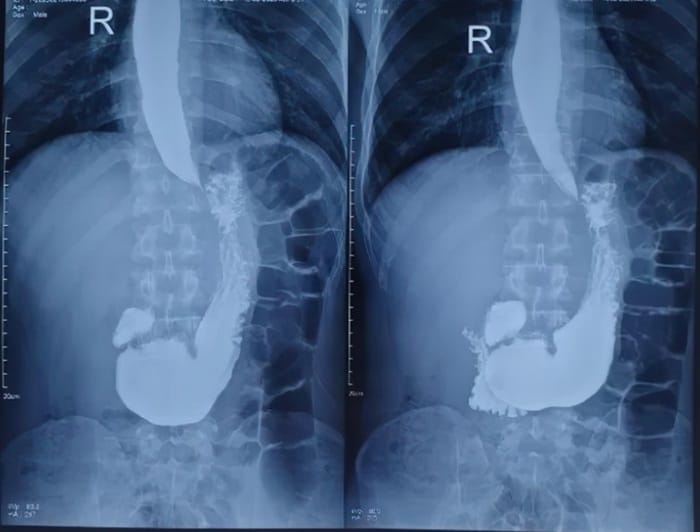

Chụp X-quang dạ dày cản quang

Bệnh nhân uống dung dịch Barium hòa tan trong nước theo hướng dẫn bác sĩ để dạ dày hiện rõ trên phim X-quang. Phương pháp này giúp phát hiện tổn thương lớn, hẹp môn vị, khối u hoặc thoát vị hoành. Tuy nhiên, các tổn thương nhỏ, viêm nhẹ hoặc polyp có thể không được phát hiện.

Chụp X-quang dạ dày có cản quang giúp phát hiện tổn thương lớn